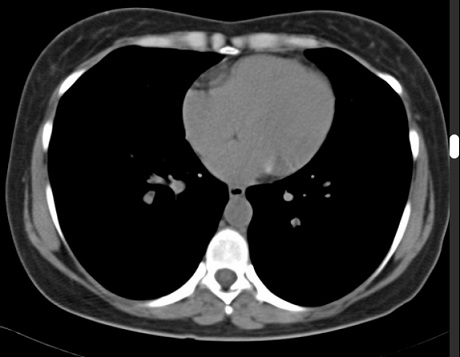

Image

radiologique TDM normale en coupe axiale , fenetre

mediastinale ( osseuse ) . Le parenchyme du poumon

en vue de moins nette et en moindre de detail de parenchyme pulmonaire |

|

Même cas en fenêtre parenchymateuse La

parenchyme du poumon , artere, veine pulmonaire et

les deux bronche hilaire etre en vue tres nette .

Image radiologique TDM en coupe axiale , fenêtre

parenchymateuse |